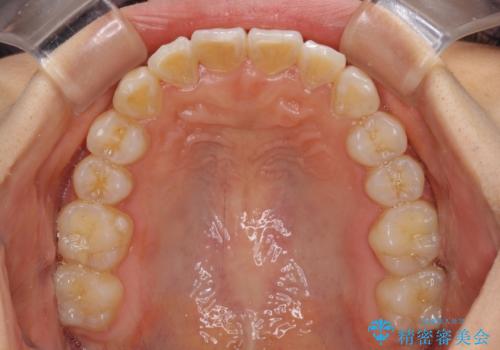

- 上下のデコボコと前歯のクロスバイトを改善したいとのことで来院された患者様です。

極力短期間で治療したいとのことで、ワイヤー装置による矯正治療を行うこととしました。

お住まいが遠方であったため、マウスピースによる矯正治療も提案しましたが、ご自身でのマウスピースの管理の面倒くささと、なるべく早く治療を終えたいとのことで、ワイヤー矯正を選択されました。